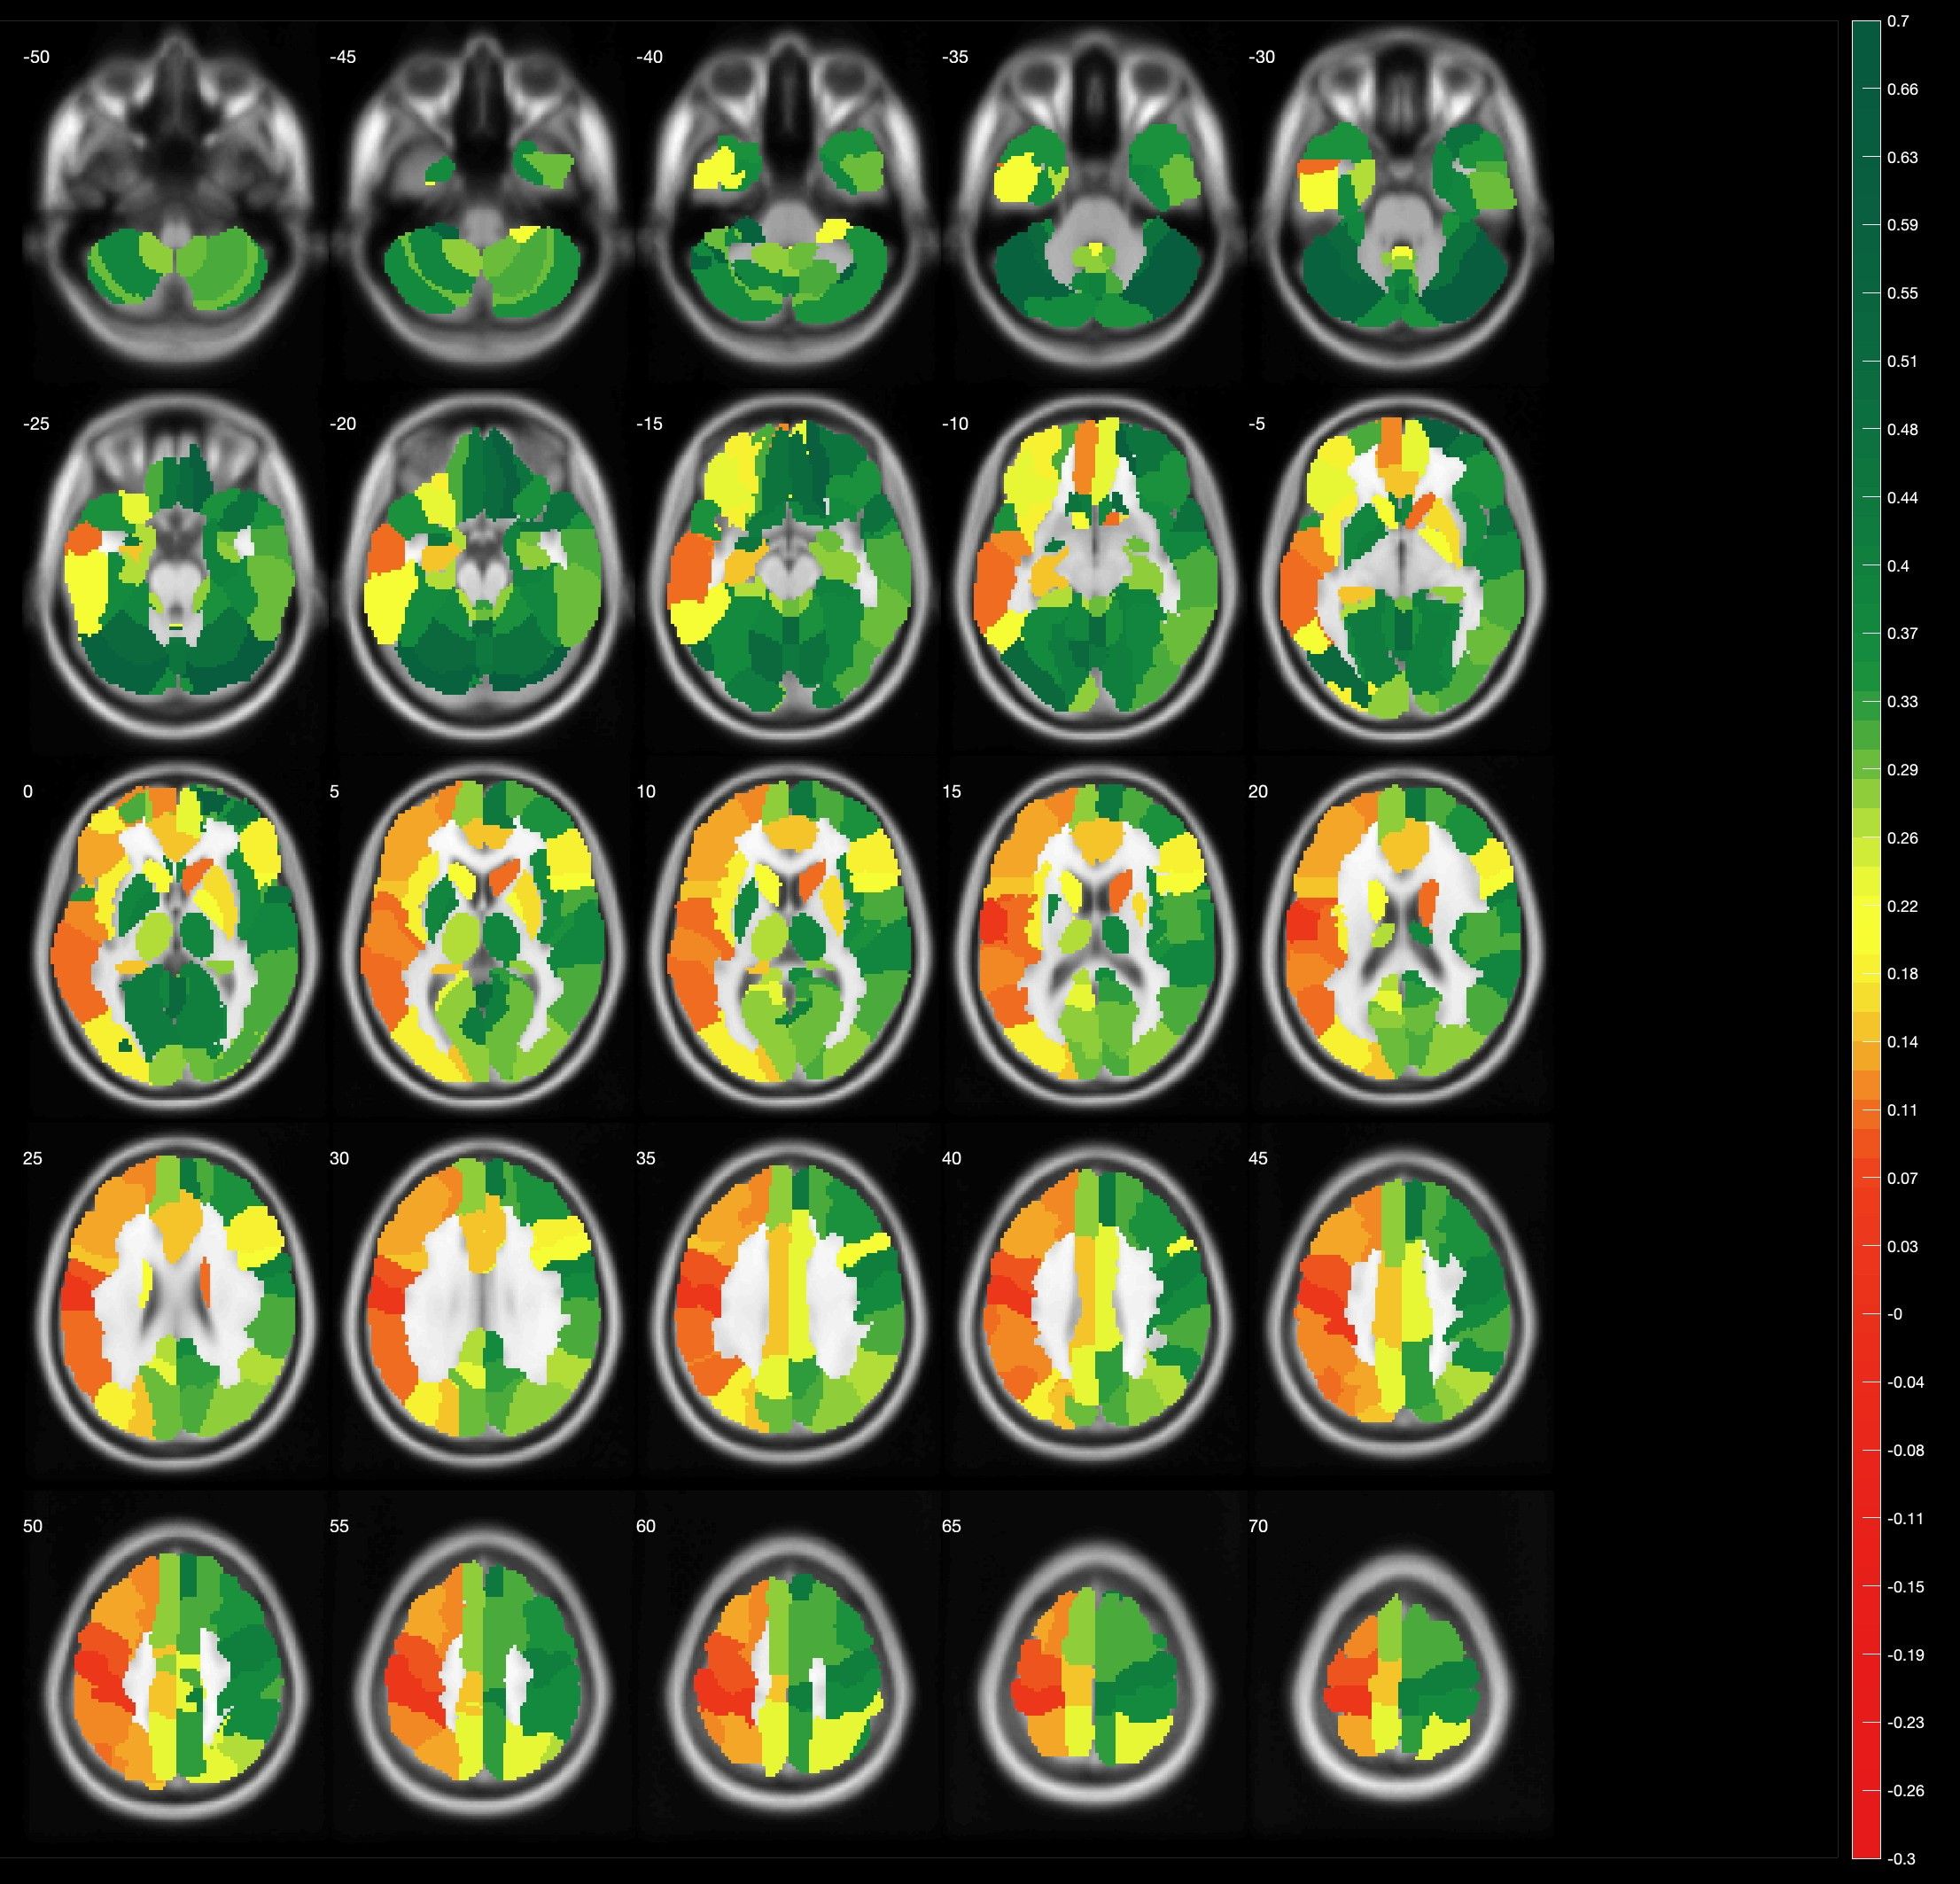

Darstellung im breathhold fMRT

Anatomische Darstellung der Hirndurchblutung gemessen im breathhold fMRT. Grüne Farbe zeigt eine regelhafte Durchblutung an, während die rötlicheren Farben eine unzureichende Hirndurchblutung anzeigen. Auffällig hierbei die Durchblutung im mittlere Hirnareal rechts (hellgrüne Kurve) im Vergleich zu allen anderen Hirnarealen und dem Kleinhirn (Cerebellum – gelbe Kurve), welches als Referenz dient.